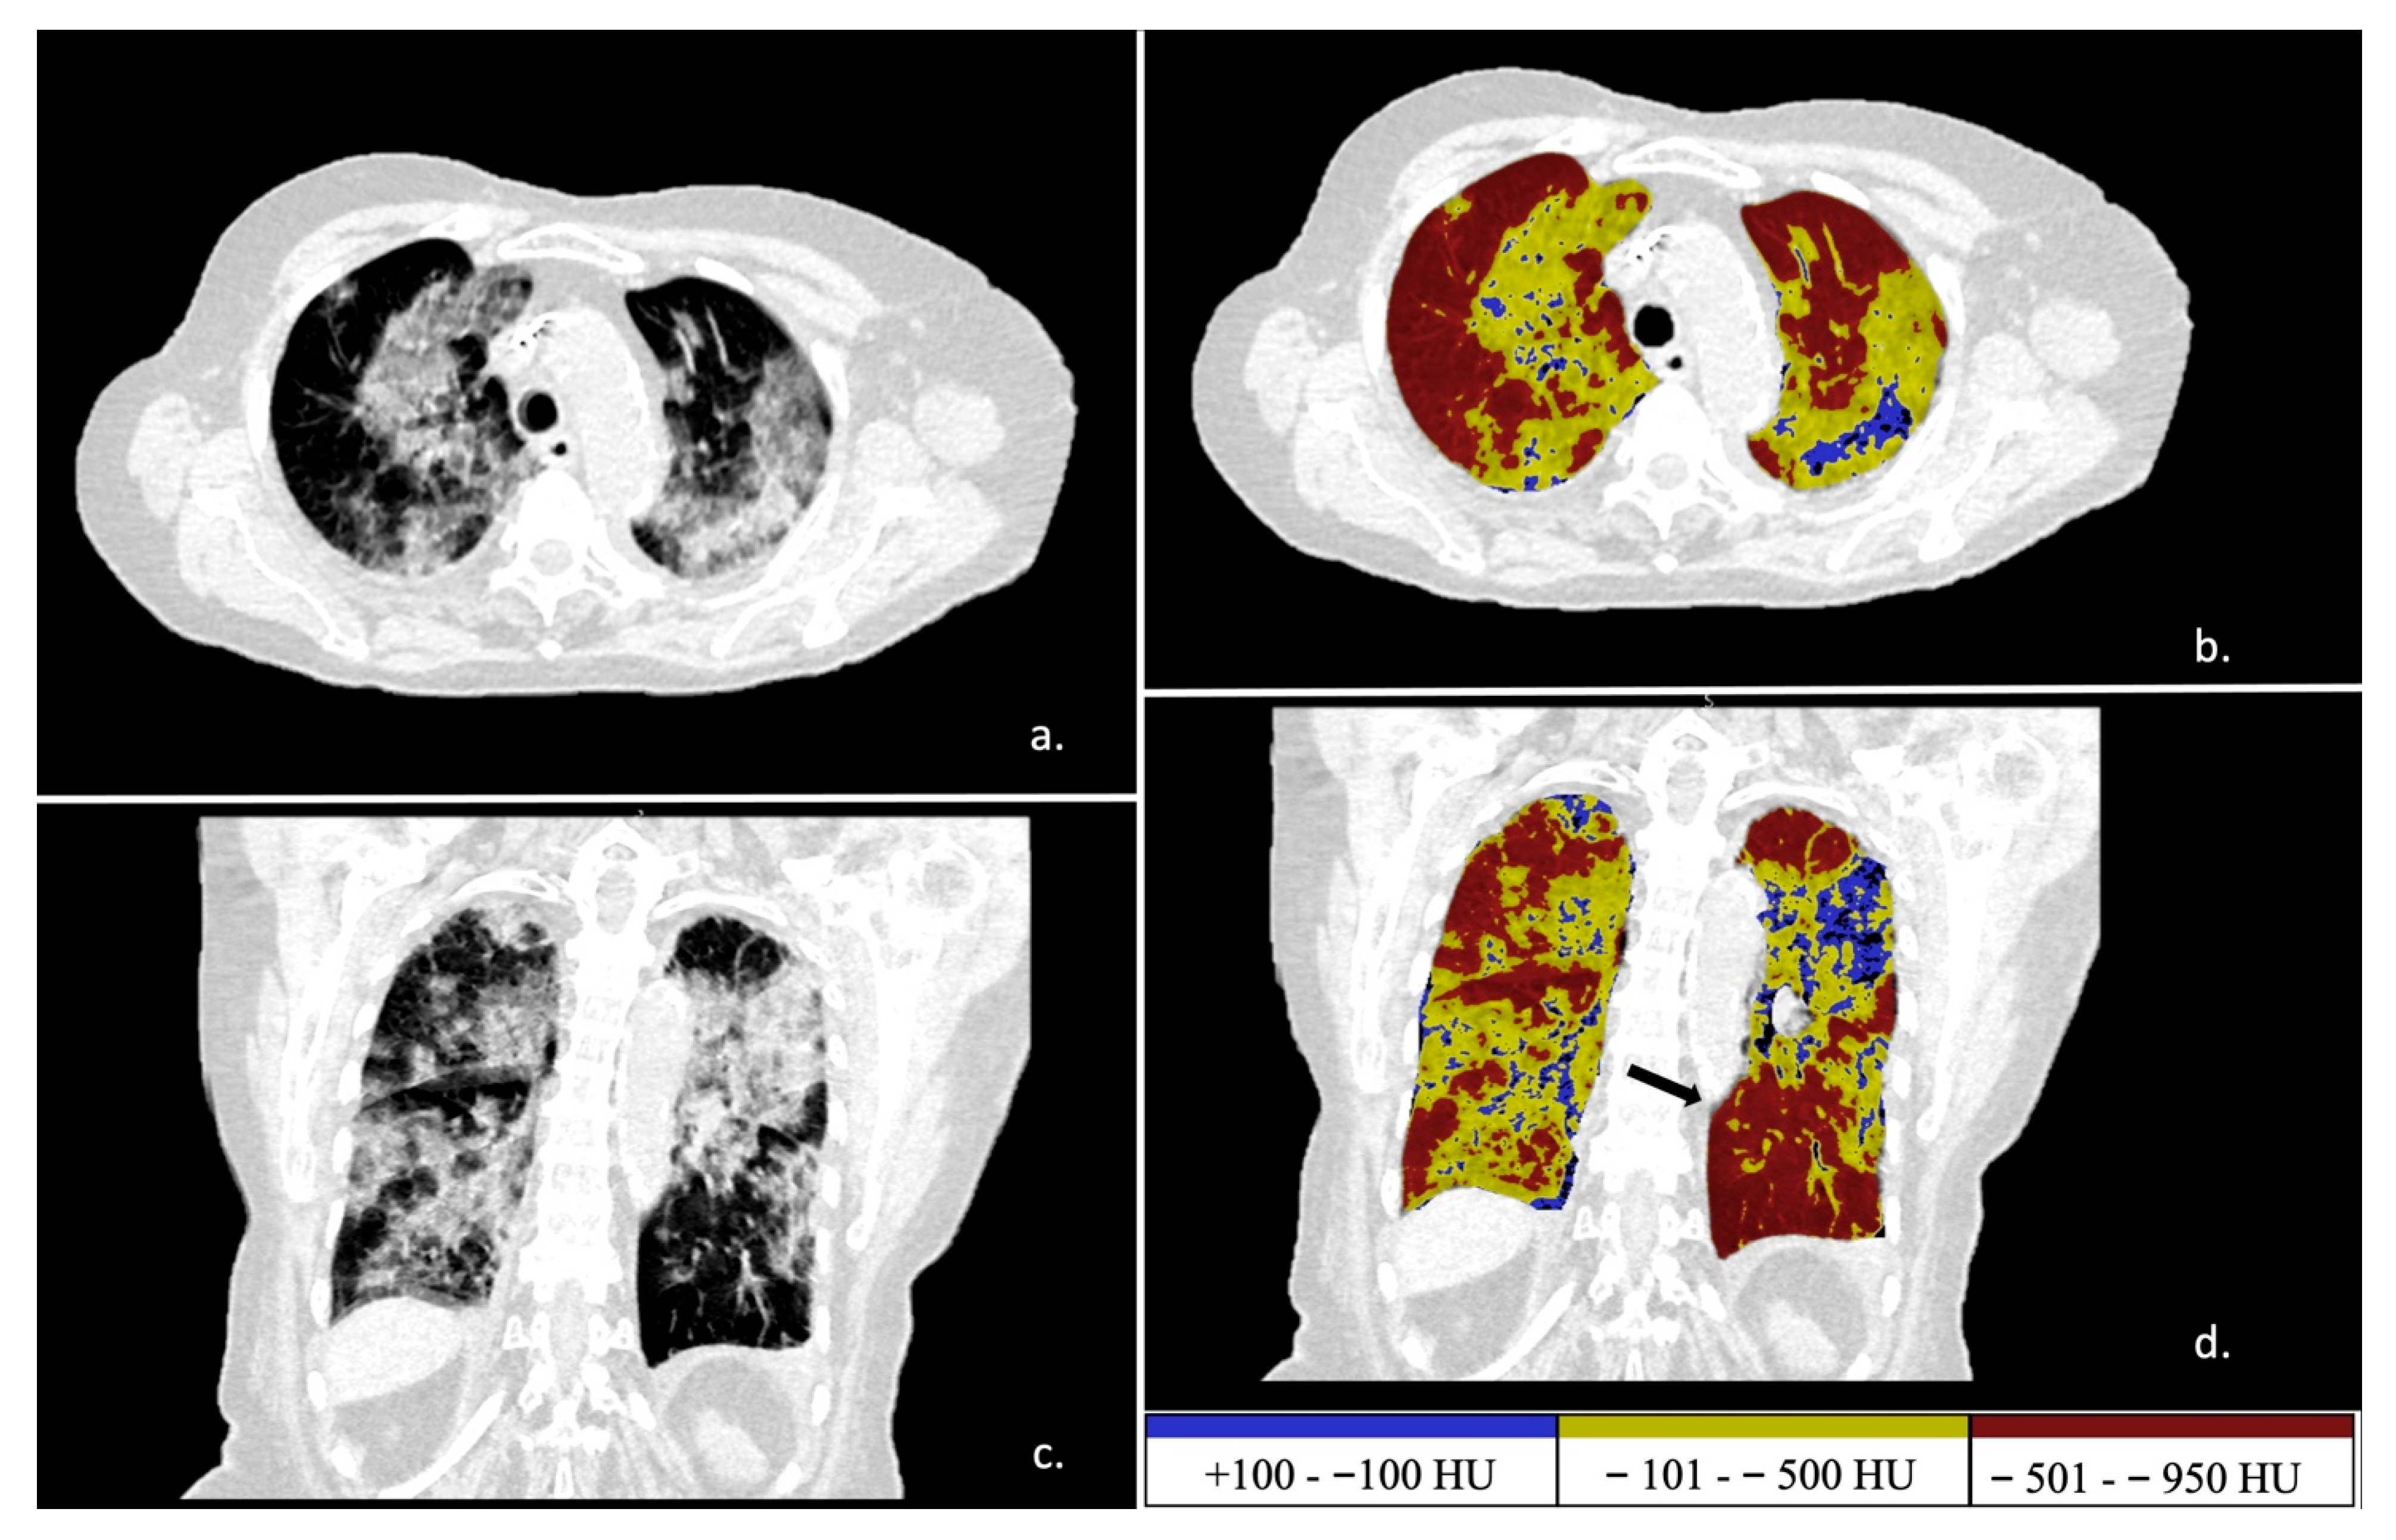

2.2. Postprocessing Analysis